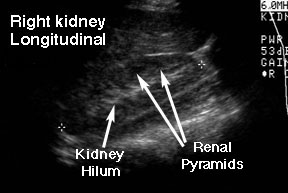

This is a longitudinal view of a right kidney (the bean-shaped structure between the two tiny crosses). Notice that the renal parenchyma is not homogeneous. The cortex (the periphery of the kidney tissue) is grey with some darker circles spaced uniformly around the edge. These darker circles are the renal pyramids. The lighter grey to white area in the center of the kidney is the hilum. This area generates a lot of echoes because there are so many types of tissue in that area: arteries, veins, collecting system, nerves and lymphatics.